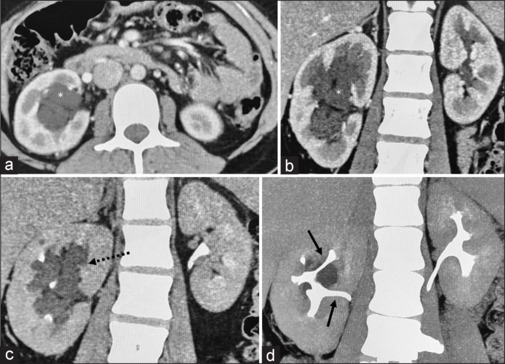

肾淋巴管扩张是一种良性疾病,其特征是肾脏淋巴管囊性扩张。它可发生在肾周、肾窦和肾内。我们描述一个罕见的病例肾窦淋巴管扩张与特征性的影像学表现在一个25岁的女性。她表现为腰部疼痛,并进行了保守治疗。

Renal lymphangiectasia is a benign disorder characterized by cystic dilatation of lymphatic channels in the kidney. It can occur in the perinephric, renal sinus, and intrarenal locations. We describe an uncommon case of renal sinus lymphangiectasia with a characteristic imaging appearance in a 25-year-old female. She presented with loin pain that was managed conservatively.